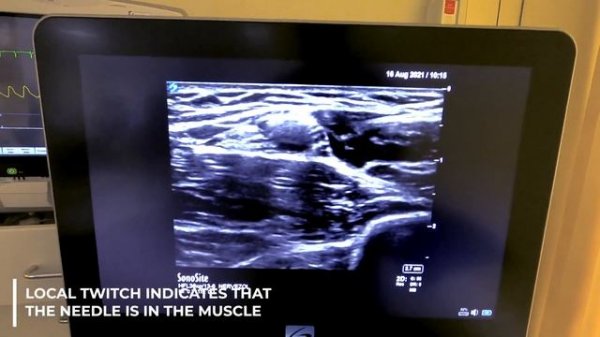

Axillary Block Decision Making Explained - Crash course with Dr. Hadzic

Axillary Plexus Block: Decision Making- Crash course with Dr. Hadzic